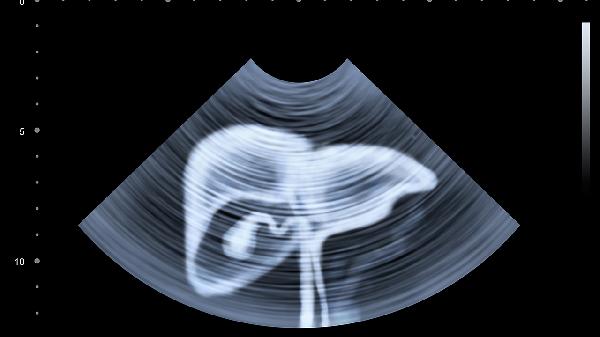

有乙肝/丙肝病史、长期酗酒、家族有肝癌患者的人群,建议每6个月做一次腹部B超+甲胎蛋白检查。当出现上述任何症状持续两周不缓解,别犹豫,立即挂消化内科或肝病科就诊。现代医学对早期肝癌的治疗手段已经很成熟,关键就在于及时发现那稍纵即逝的身体信号。